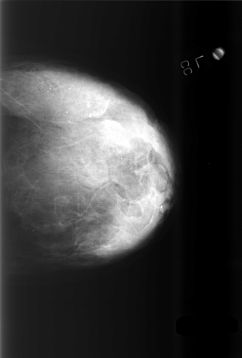

ics_version 1.0 filename C-0505-1 DATE_OF_STUDY 22 12 1998 PATIENT_AGE 57 FILM FILM_TYPE REGULAR DENSITY 4 DATE_DIGITIZED 25 2 1999 DIGITIZER LUMISYS LASER SEQUENCE LEFT_CC LINES 5728 PIXELS_PER_LINE 3872 BITS_PER_PIXEL 12 RESOLUTION 50 NON_OVERLAY LEFT_MLO LINES 5784 PIXELS_PER_LINE 3856 BITS_PER_PIXEL 12 RESOLUTION 50 NON_OVERLAY RIGHT_CC LINES 5800 PIXELS_PER_LINE 3936 BITS_PER_PIXEL 12 RESOLUTION 50 OVERLAY RIGHT_MLO LINES 5872 PIXELS_PER_LINE 3704 BITS_PER_PIXEL 12 RESOLUTION 50 OVERLAY |